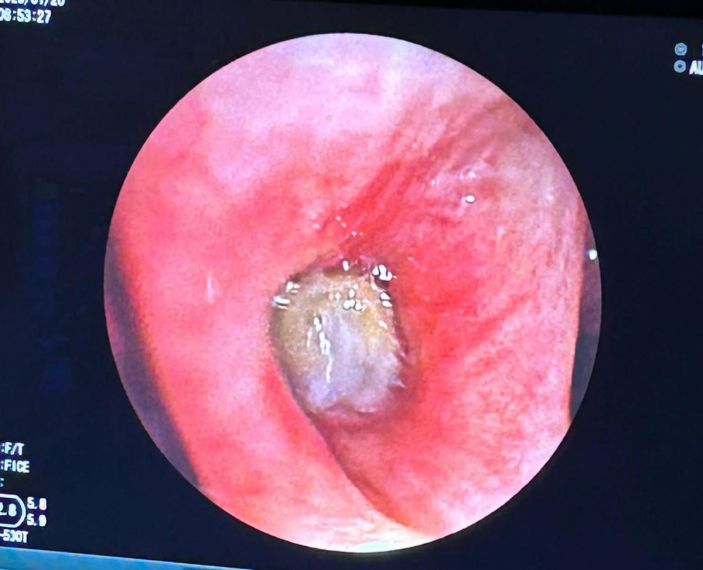

Doç. Erhan Uğurlu’nun muayene ettiği Yurteri’nin hava resimlerini görüntülemek için yapılan fiberoptik bronkoskopi işlemi sırasında beklenmeyen görüntüyle karşılaşıldı.

hastaların sağ taramalarında, bulunduğu hava yolunu kapatan hücreler tanesi farklı bulundu.

Yurteri’nin taramalarındaki tahıl parçalarını ameliyatla çıkarın.

Aspirasyon denilen cüruf yabancı cisimlerin kaçmasının genellikle çocuklarda beklense de düşük boyutlarda de görülebiliyor. Bezelye tanesi olması nedeniyle hava yolunda küçük bir tıkanıklığa yol açan hastalarda bulgu veren yabancı cisim aspirasyonlarının kül, balgam, hırıltı gibi yakınmalara, zatürre, akciğerde sönme gibi yuvalara da yol açabilir. Hem KOAH’a yönelik bronkoskopik volüm küçültme bobin noktasında hem de taramaya kaçan ampul taneleri alacağı hasta, sonrasında izleminde sorun görülmedi. Hastayı kontrollerine gitmek üzere taburcu ettik.